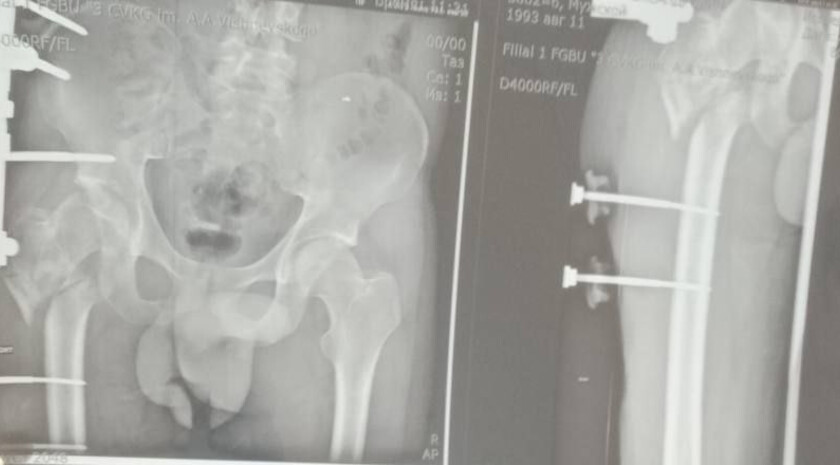

Мобилизованный 25 февраля 2022 года, военнослужащий прошел через горнило Херсонщины. 28 августа 2022 года в 23:10 под ракетным обстрелом боец получил тяжелейшее ранение правого бедра. В июле 2024 года сержант, удостоенный медали «За отвагу», был уволен со службы по состоянию здоровья.

Из-за обширных повреждений и многократных операций правая нога бойца стала короче левой на восемь-девять сантиметров. Обычное эндопротезирование изменить ситуацию не могло.

«Требовалось чудо инженерной и хирургической мысли. Чудо произошло 5 марта 2026 года в Луганске. В Луганской республиканской клинической больнице бригада травматологов-ортопедов провела операцию, которая стала финальным аккордом этой долгой истории. Вместо стандартной замены сустава пациенту выполнили сложнейшее вмешательство с использованием ревизионных систем эндопротезирования, в ЛНР такую операцию провели впервые», — проинформировала Пащенко.

Она уточнила, что главная задача хирургов заключалась не просто в установке импланта, а в восстановлении биологической оси конечности и компенсации укорочения.

Хирургам пришлось работать в рубцово-измененных тканях после десятка предыдущих операций, убрать очаги инфекции и с помощью специальных ревизионных компонентов буквально «собрать» сустав заново, вернув ноге физиологическую длину.